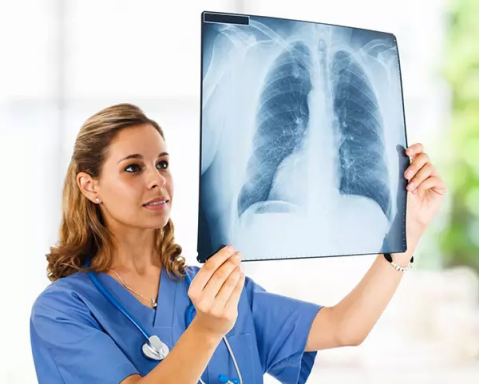

X光攝影(平片)

X光會穿透人體,由于人體各部位組織密度厚度不同,吸收的X光機(jī)的劑量不同,到達(dá)底片的X光的量不同,底片就會顯現(xiàn)出黑白不同的顏色。

優(yōu)點:快捷、價廉、影像清晰度高

缺點:平片檢查,無法進(jìn)行三維檢查

3、胸部——粗看X光平片,細(xì)看CT

X光胸片可粗略檢查肺、心影、主動脈弓、肋骨等,可以檢查有無肺紋理增多、肺內(nèi)較大腫塊、主動脈結(jié)鈣化等。胸部CT檢查顯示出的結(jié)構(gòu)更清晰,對胸部病變檢出敏感性和準(zhǔn)確性均優(yōu)于常規(guī)X光胸片,特別是對于篩查早期肺癌有重大意義。而磁共振成像對于肺內(nèi)疾病的診斷,應(yīng)用非常有限。